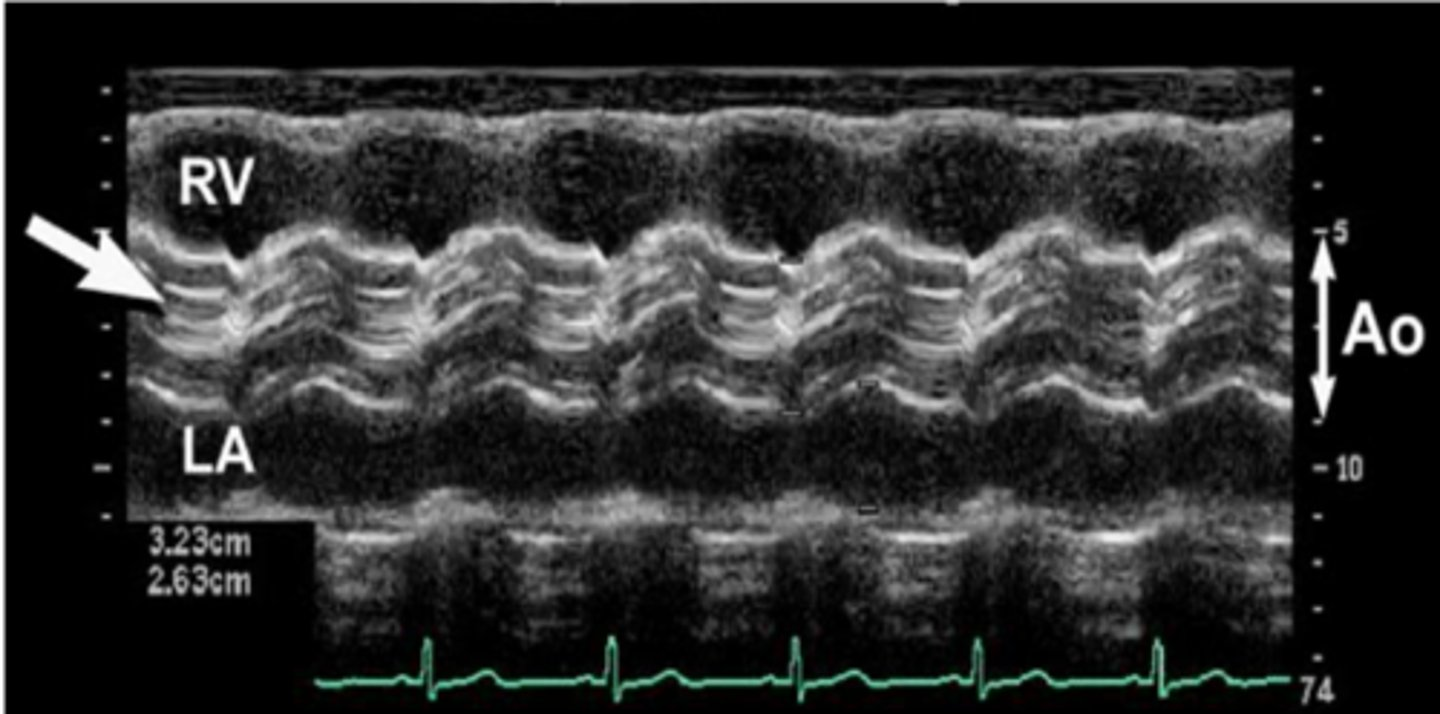

larger than 1:1 ratio between LA and AOR with larger AOR

dilated aortic root

larger than 1:1 ratio between LA and AOR with larger LA

dilated left atrium